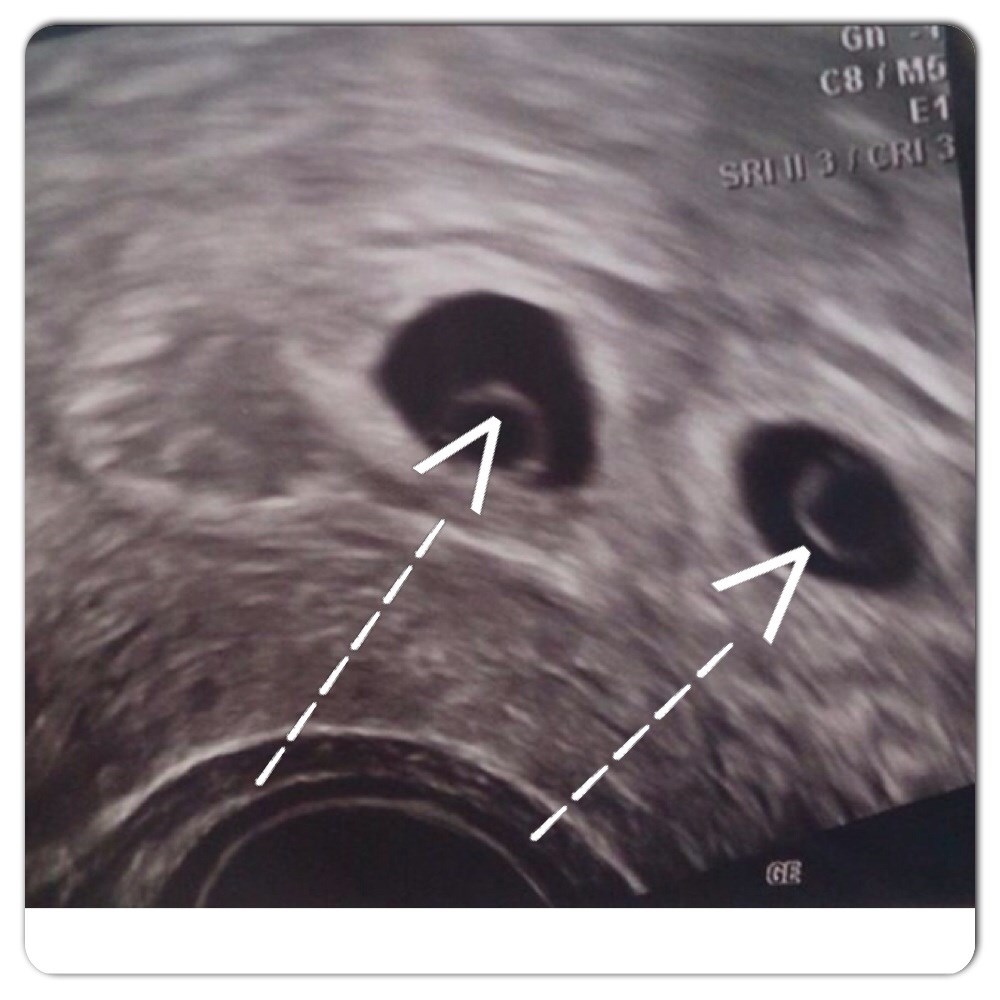

Det er disse runde ringe der gerne skulle udvikle sig til babyer, derfor tror vi ikke på at de er tomme dine blommesæk.

Vedhæftede fotos (klik for at se i fuld størrelse)

Man kan jo tydeligt se "noget rundt" inde i blommesækkene.

Jeg skal ikke kunne sige hvad de runde inde i dine blommesække betyder - men ja, de ligner de scanningsbillieder du viser fra uge 5. Men da du har været i behandling, kan man jo fastslå meget præcist hvor lang du er henne, så det giver ikke rigtigt mening at du skulle være to uger mindre end forventet.